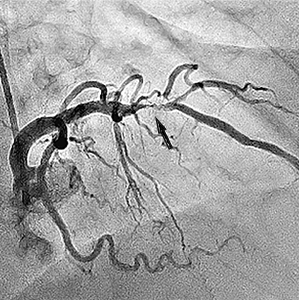

Приклади коронарограм:

стеноз правої коронарної артерії    стеноз лівої коронарної артерії

Звуження (стеноз)

правої коронарної артерії

Звуження (стеноз) гілки

лівої коронарної артерії.